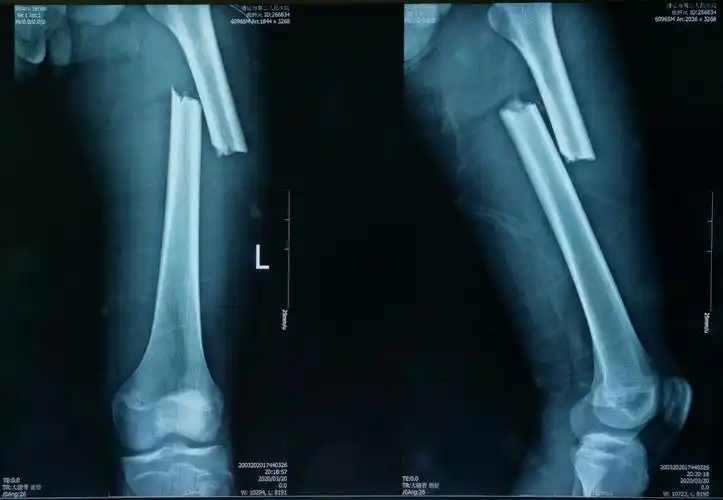

股骨干骨折闭合复位髓内钉内固定手术一例